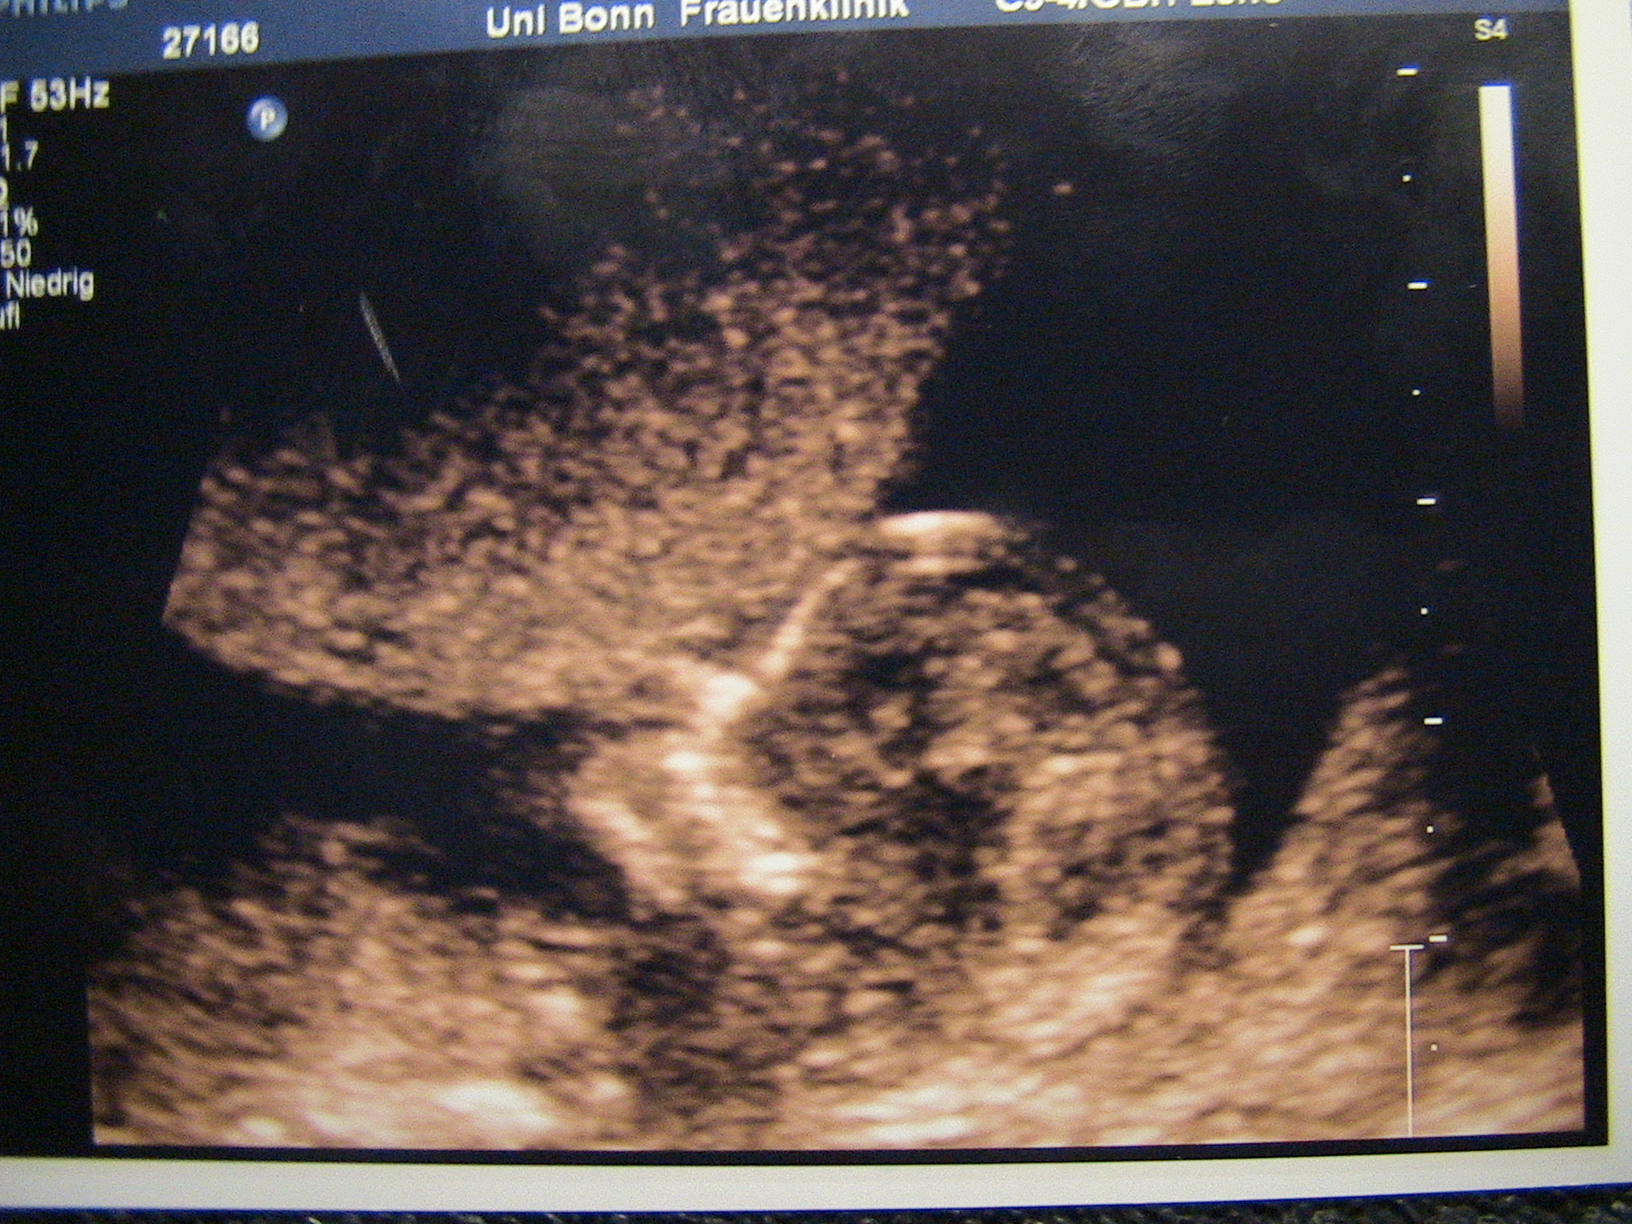

Jaqueline: Ich freu mich wirklich wahnsinnig für euch!!! Gratulation zur NFM und zum Jungen und überhaupt!!!!

@Jaqueline: Wie süüüüüüüüüüüss!! So ein kleines Würmchen!!!

@Jaqueline: Herzlichen Glückwunsch zum Sohnemann!!!!! Jetzt schon lässig euer Kleiner, im Schneidersitz mit den Füssen winkend!!!

@Jaqueline: Herzlichen Glückwunsch zum Sohnemann!!!!! Jetzt schon lässig euer Kleiner, im Schneidersitz mit den Füssen winkend!!!COOL!!!!